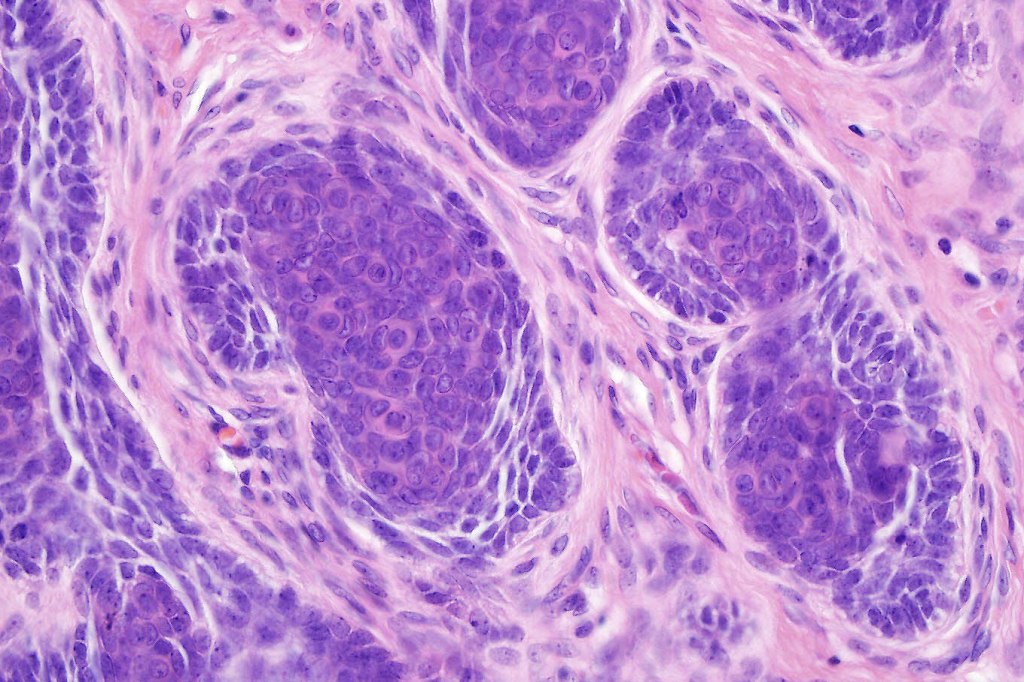

•Variably sized but generally large, basophilic tumor nodules composed of small uniform basaloid cells with minimal cytoplasm

•Peripheral palisading but no retraction artifact or stromal mucin deposition

•A rich fibromyxoid mesenchymal stroma with variable papillary mesenchymal bodies (sometimes these are absent)